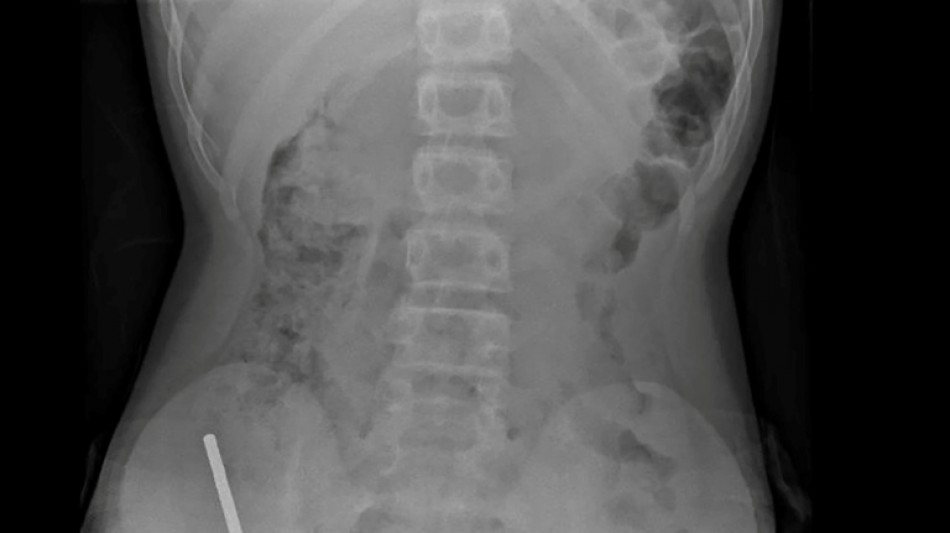

An X-ray showed the magnets had clumped together in four straight lines inside the child's intestines.

"These appeared to be in separate parts of bowel adhered together due to magnetic forces," they said.

Doctors said the pressure of the magnets had caused necrosis -- tissue death -- in four areas of the boy's small bowel and caecum, which is part of the large intestine.